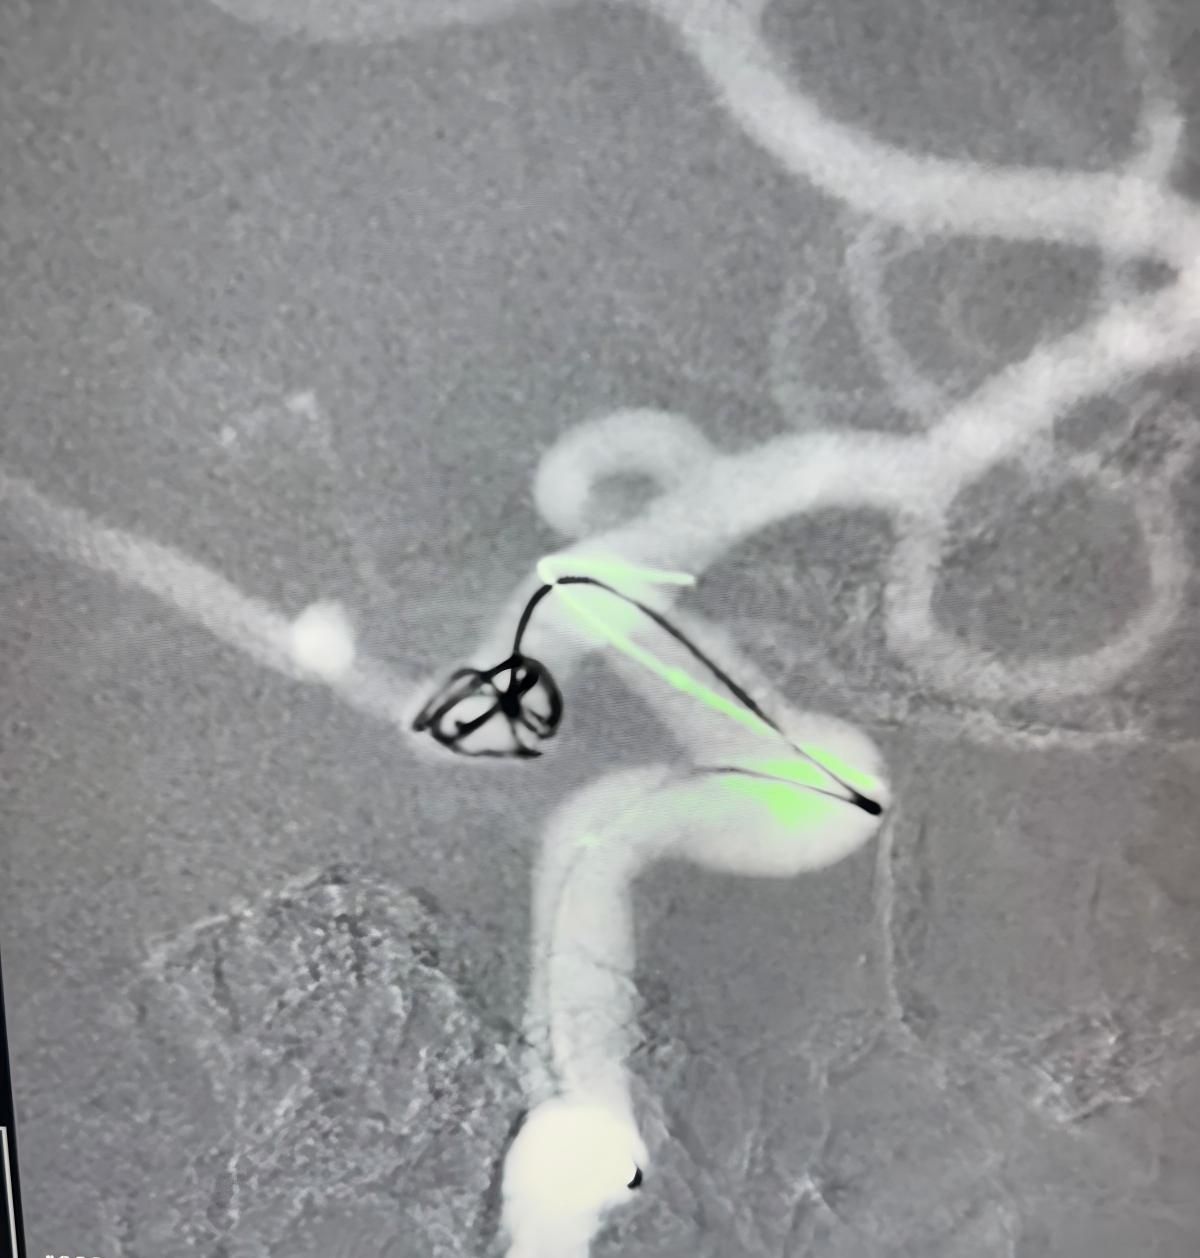

Siamo lieti di condividere una recente procedura di successo presso Clínica Alma Mater, Medellín, eseguita dal Dr. Jorge Mutis.

Il trattamento ha utilizzato la Nuva®Deviatore di flusso (TJED-D 5.0-14), Perdenser®Bobina 3D e Fepass®Microcatetere (TJMC18 Plus) per un aneurisma dell'arteria comunicante posteriore.

Il dottor Mutis ha evidenziato l'eccellente visibilità del dispositivo e ha notato che il recupero è stato regolare. Ha espresso grande soddisfazione per l'esito finale.